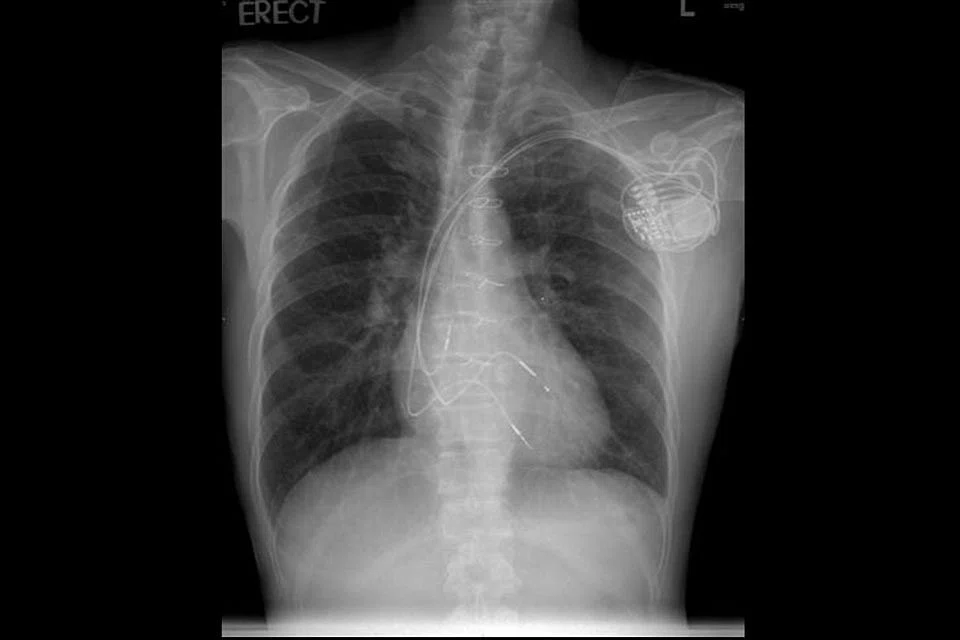

Preventing sudden cardiac death

Whether young or old, one needs to take precautionary measures against the silent killer